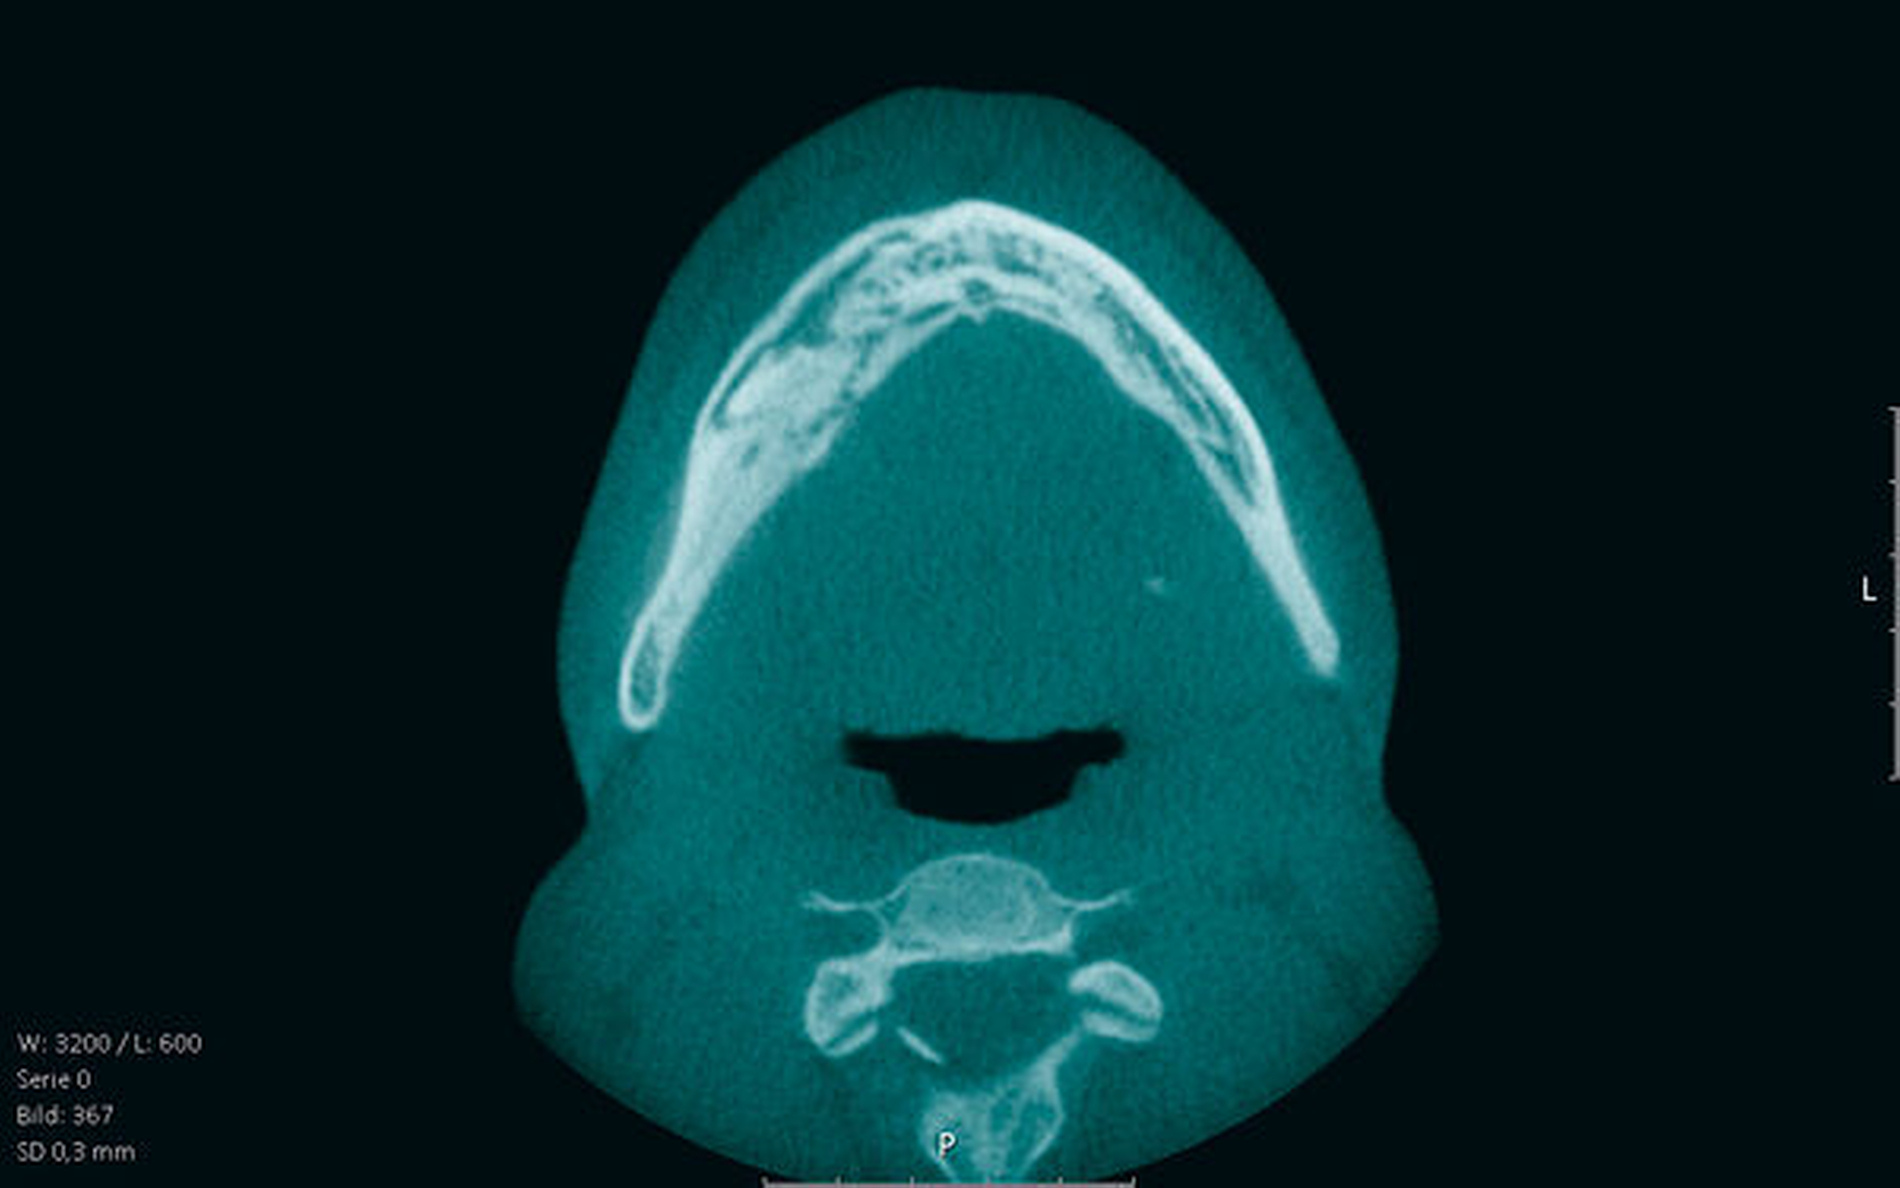

Im Ergebnis wies die Knochenszintigrafie eine höhere Traceraufnahme in Arealen auf, an denen sich später eine MRONJ entwickelte. Bei Patienten im Stadium 0 zeigte sowohl die 2-D- als auch die 3-D-Bildgebung Sklerosierungen, Veränderungen in der trabekulären Ausrichtung, Osteolysen, fleckig erscheinende Knochenstrukturen, eine verdickte Lamina dura, persistierende Extraktionsalveolen und Veränderungen um den Canalis mandibularis. Die 3-D-Bildgebung konnte periradikuläre Radioluzenzen, kraterartige Defekte, eine verdickte mandibuläre Kortikalis, Knochensequester und Unregelmäßigkeiten in der ossären Kortikalis besser darstellen. Die Frage nach dem Zeitpunkt des Beginns der Knochenveränderungen beantwortete die Literatur nicht. Eine Assoziation zwischen Knochenveränderungen und Art/Dosis der antiresorptiven Medikation ließ sich ebenso wenig wie der Zusammenhang zwischen den knöchernen Veränderungen und der Entwicklung einer MRONJ bei Risikopatienten und Patienten im Stadium 0 aus Einzelstudien nachweisen.

Zusammengefasst verändert die Einnahme antiresorptiver Medikamente radiologisch erkennbar die Kieferknochenstruktur, wobei Sklerosierungen am häufigsten zu finden sind. Die umfangreiche Arbeit unterstreicht die Notwendigkeit, bei Patienten unter antiresorptiver Medikation – am besten vor der ersten Einnahme und vor einer zahnärztlichen Behandlung – eine radiologische Basisuntersuchung im Kieferbereich durchzuführen, die im Verlauf als Grundlage für die Nachsorge dienen kann.